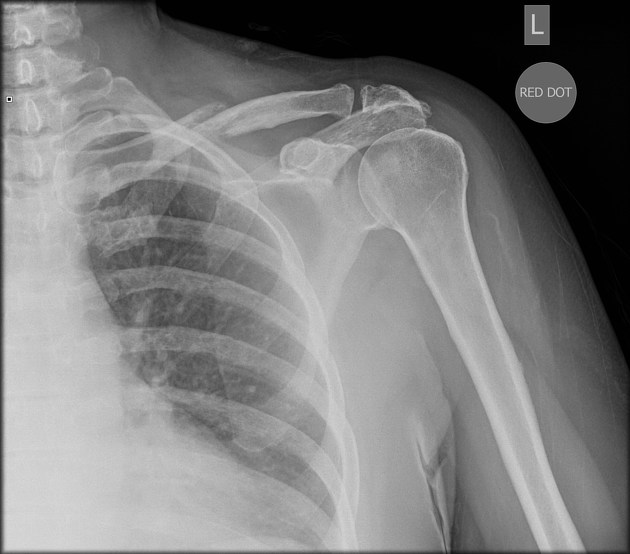

Describe the abnormality demonstrated.

Salter-Harris type 1 fracture of the left shoulder with complete medial displacement.

Also left ACJ widening and an incomplete mid-shaft fracture of the left clavicle.